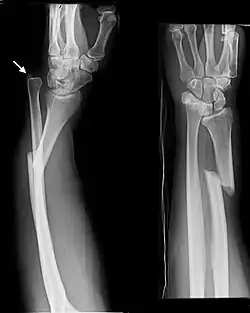

An ulna fracture is a break in the ulna bone, one of the two bones in the forearm.[2] It is often associated with a fracture of the other forearm bone, the radius.[1][3]

The diagnosis of an ulna fracture is made after taking the persons history, which usually includes a history of forearm pain following trauma, and then examining the injured forearm followed by an x-ray of the relevant part.[5]

Fractures of the ulna can occur at different levels of the bone: near the wrist, in the middle or near the elbow.[2] The fracture may be confined to the ulna or accompanied with damage to the radius or the wrist or elbow joints.[2]